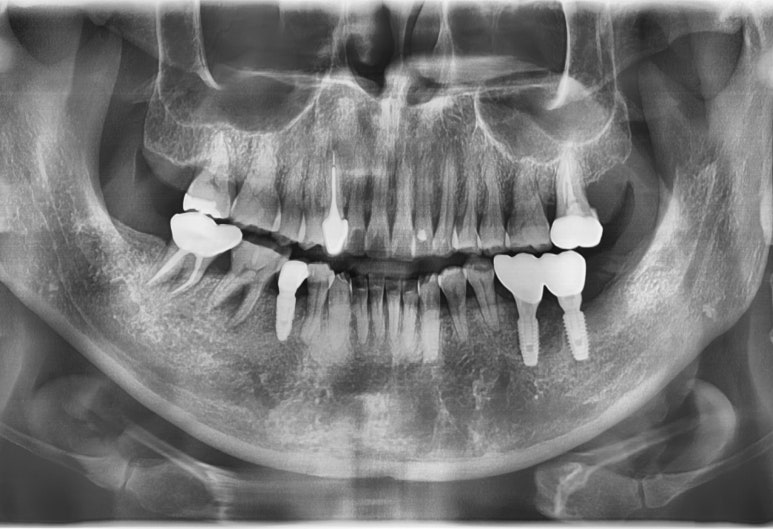

아래 사진의 환자분은 임플란트 주변 뼈가 녹아서

임플란트 픽스쳐부분이 뼈와 붙어있지 않아 흔들리는 상태였습니다.

처음 내원시

오래된 임플란트 2개를 제거하고

옆에 흔들리는 이까지 발치 한 후

재수술 임플란트는 2개를 심고 머리3개짜리를 완성하였습니다.